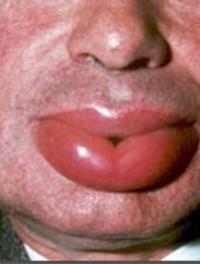

L’urticaire chronique spontanée (UCS) désigne la présence de lésions d’urticaire prurigineuses parfois associées à un angioœdème pendant [...]